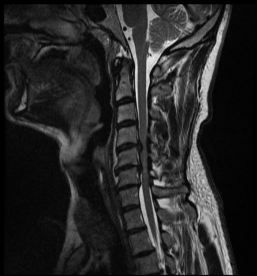

Spinalkanalstenose I

MRI with lateral reconstruction of the lumbar spine. The hourglass-like narrowing of the spinal canal can be seen at two heights.